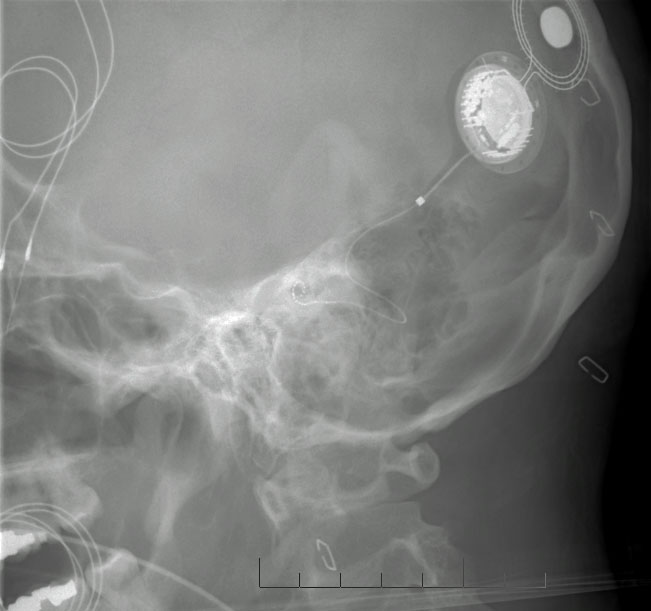

The operation

Video: Sequential bilateral cochlear implantation surgery, with captions and transcript (From University Hospitals Case Medical Center, Cleveland, OH. Feb 24, 2009) After the jump, click on High Bandwidth under the video screen, it seems to play better.

Video: A step by step guide from Mr Lujber ENT surgeon from Pecs University ENT department Hungary (February 2012).